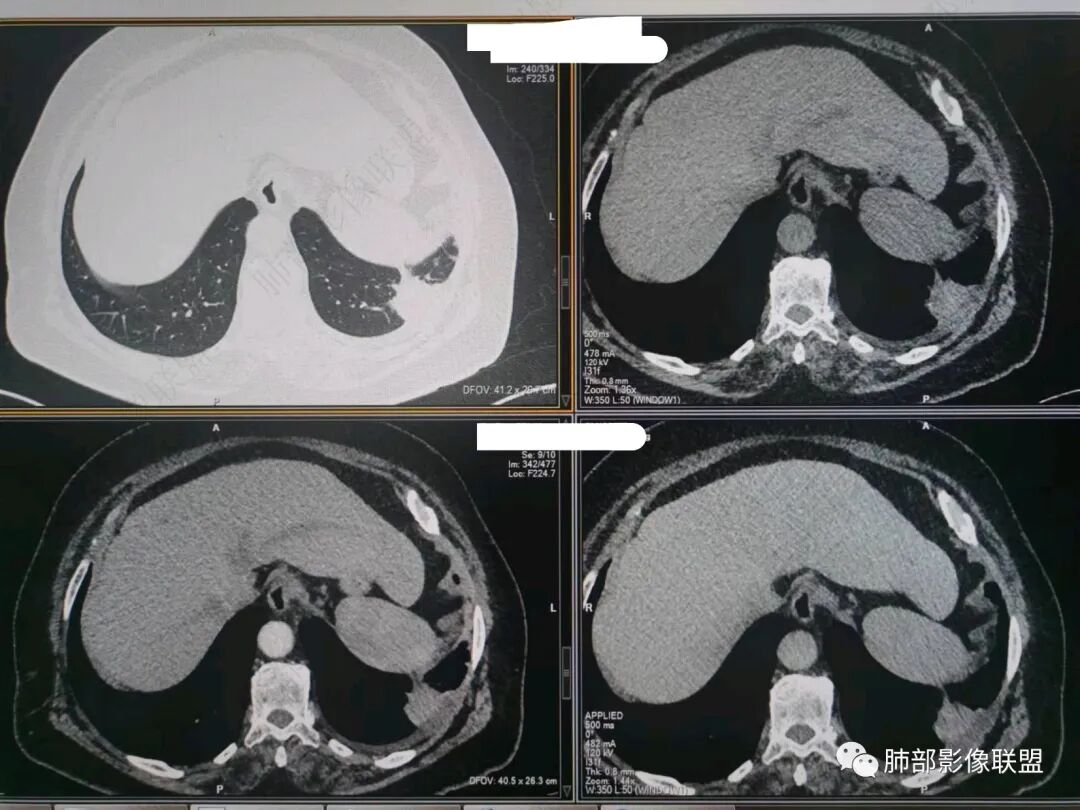

南边:今天的病例肺内部分基本都是炎性特点,问题就在于胸膜。

糊墙:肺内病灶不侵犯壁层胸膜或以外,与壁层胸膜相对而言分界清楚。

栽赃:病灶侵入壁层胸膜及胸膜外脂肪间隙、胸壁其他结构等,相对在病灶中央区域,与胸膜分界不清。

南边:看肺内病灶与胸膜分界清,增强后强化不一致,需要综合分析。

这是糊墙。

这就栽赃。都突到外面去了。

看看这个,骨头都侵袭了。

我就不知道这些是胸水,伪影导致密度增高?还是胸膜增厚?

我只是邓较瘦:今天平扫的像栽赃, 增强感觉是增厚的胸膜。

南边:一般这类侵袭,是中央地带毛刷状延伸到胸膜内。

而且旁边这么宽的少,所以觉得很奇怪,不太符合,我是怀疑与照片有关。

你对比一下两侧的密度。肌肉密度不一样。